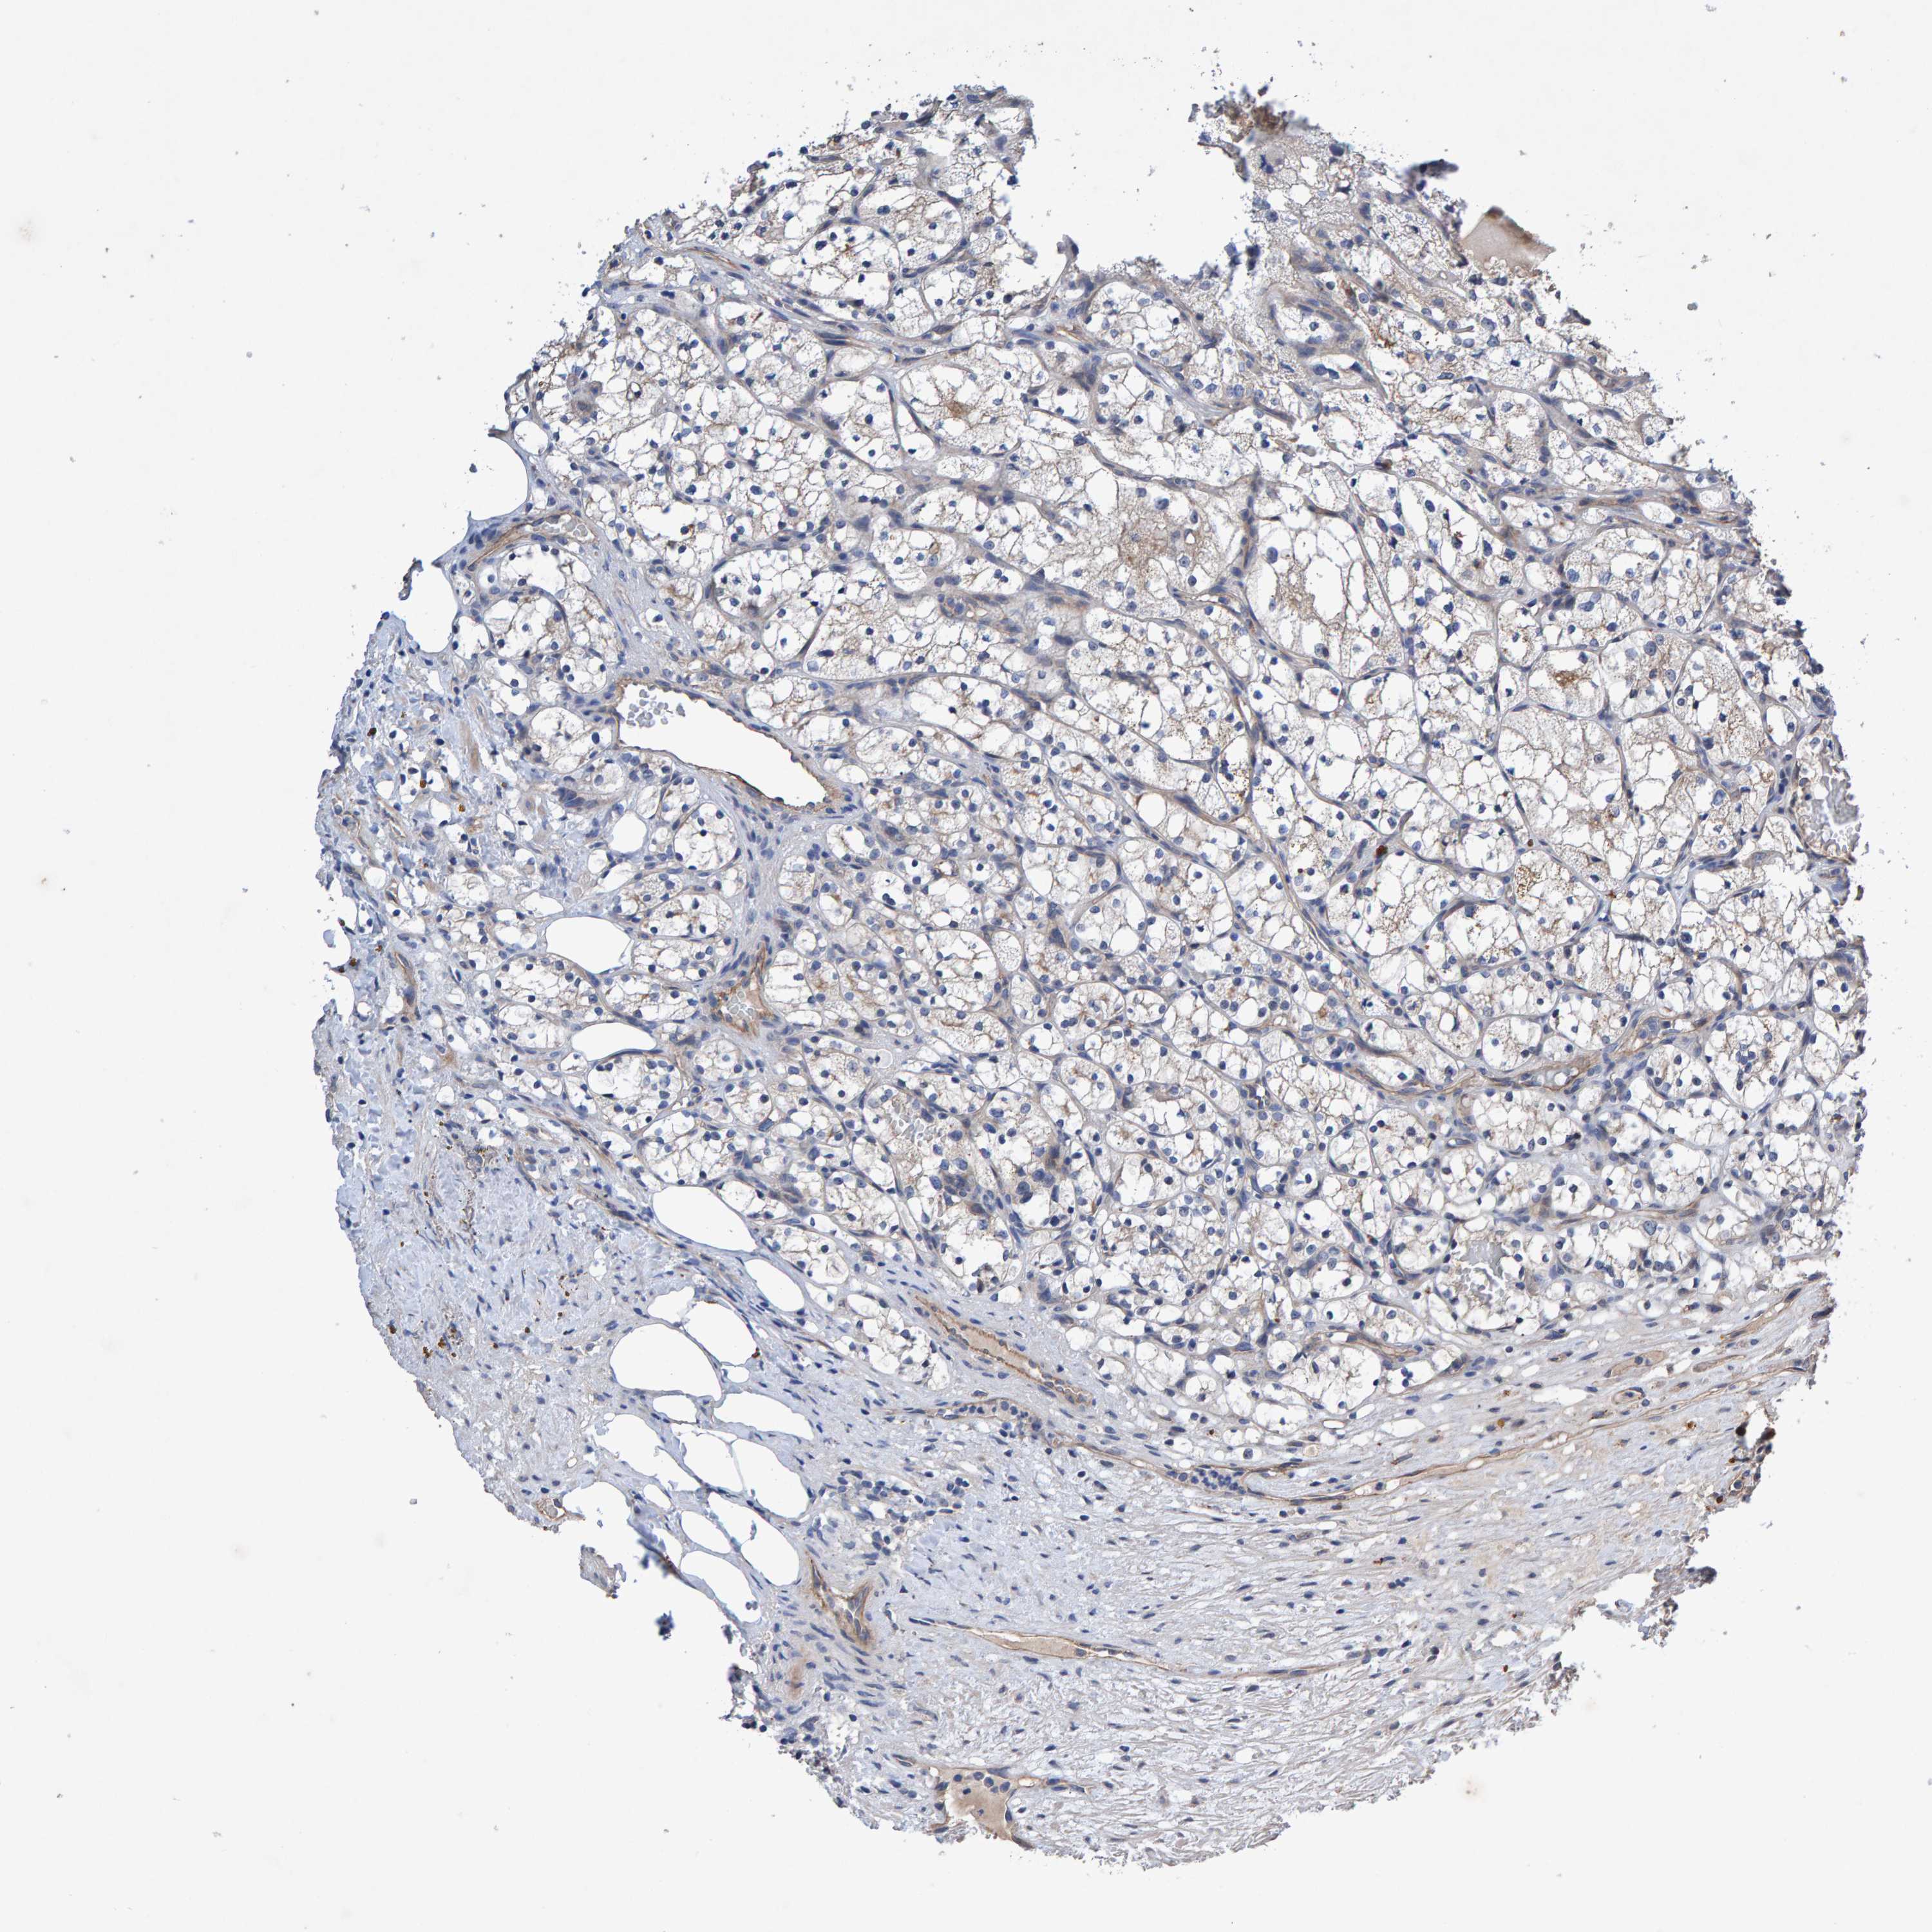

KIDNEY RENAL CLEAR CELL CARCINOMA (TCGA) - Interactive survival scatter ploti

The Survival Scatter plot shows the clinical status (i.e. dead or alive) for all individuals in the patient cohort, based on the same data that underlies the corresponding Kaplan-Meier plots. Patients that are alive at last time for follow-up are shown in blue and patients who have died during the study are shown in red.

The x-axis shows the expression levels (FPKM) of the investigated gene in the tumor tissue at the time of diagnosis. The y-axis shows the follow-up time after diagnosis (years). Both axes are complimented with kernel density curves demonstrating the data density over the axes. The top density plot shows the expression levels (FPKM) distribution among dead (red) and alive patients (blue). The right density plot shows the data density of the survived years of dead patients with high and low expression levels respectively, stratified using the cutoff indicated by the vertical dashed line through the Survival Scatter plot. This cutoff is automatically defined based on the FPKM cutoff that minimizes the p-score. The cutoff can be changed by dragging the vertical line or by entering a cutoff value in the square labeled "Current cut-off".

Under the Survival Scatter plot the p-score landscape (black curve; left axis) is shown together with dead median separation (red curve; right axis). Dead median separation is the difference in median mRNA expression between patients who have died with high and low expression, respectively. It is calculated as follows: median FPKM expression of dead patients with high expression - median FPKM expression of dead patients with low expression. This is intended to aid the user in visually exploring custom cutoffs and the associated p-scores and dead median separation.

Individual patient data is displayed and can be filtered by clicking on one or more of the category buttons on the top of the page. Categories describing expression level and patient information include: high, low, alive, dead, female, male and tumor stages. The scale of the x-axis can be toggled between linear and log-scale by clicking on the "x log" button. Mouse-over function shows TCGA ID, patient information and mRNA expression (FPKM) for each patient.

& Survival analysisi

Kaplan-Meier plots summarize results from analysis of correlation between mRNA expression level and patient survival. Patients were divided based on level of expression into one of the two groups "low" (under cut off) or "high" (over cut off). X-axis shows time for survival (years) and y-axis shows the probability of survival, where 1.0 corresponds to 100 percent.

EFR3A is potential prognostic, high expression is favorable in Kidney Renal Clear Cell Carcinoma (TCGA)

Best expression cut offi

Based on the FPKM value of each gene, patients were classified into two groups and association between prognosis (survival) and gene expression (FPKM) was examined. The best expression cut-off refers the FPKM value that yields maximal difference with regard to survival between the two groups at the lowest log-rank P-value. Best expression cut-off was selected based on survival analysis .

When clicking on this number, the vertical dashed line indicating cut-off, the interactive survival plot, and the Kaplan-Meier curve will be adjusted to show results based on the best expression cut-off.

: 20.32

Median expressioni

Median expression refers to the median FPKM value calculated based on the gene expression (FPKM) data from all patients in this dataset. When clicking on this number, the vertical dashed line indicating cut-off, the interactive survival plot, and the Kaplan-Meier curve will be adjusted to show results based on the median expression.

: N/A

Median follow up timei

Median follow up time refers to the median time (years) after diagnosis with this type of cancer, based on clinical data from all patients in this dataset.

P scorei

Log-rank P value for Kaplan-Meier plot showing results from analysis of correlation between mRNA expression level and patient survival.

N/A

5-year survival highi

5-year survival for patients with higher expression than the expression cutoff.

For melanoma and glioma, 3-year survival is shown.

5-year survival lowi

5-year survival for patients with lower expression than the expression cutoff.

TCGA RNA samplesi

RNA-seq data is reported as average FPKM (number Fragments Per Kilobase of exon per Million reads), generated by the The Cancer Genome Atlas (TCGA) .

Normal distribution across the dataset is visualized with box plots, shown as median and 25th and 75th percentiles. Points are displayed as outliers if they are above or below 1.5 times the interquartile range. FPKM values of the individual samples are presented next to the box plot.

Average pTPM 26.6

Number of samples 521